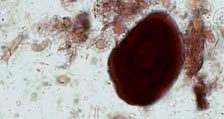

Il est fréquent de trouver des grains d'amidon dans l'urine, car toutes les poudres contiennent des grains d'amidon. Ils se présentent comme des cristaux amorphes de forme sphérique, incolores à brun pâle et fortement réfingents. Ils se colorent en rouge brun avec l'iode. En lumière polarisée ils ont un aspect de "pseudo-croix maltaise" , mais leur réfingence est différente de celle des lipides.

Grain d'amidon. Microscope à fond clair |